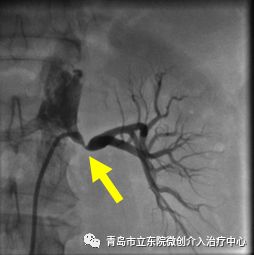

介入手术开始,穿刺患者右侧大腿的股动脉,通过2mm左右的穿刺孔送入导管,术中造影确认,左侧肾动脉重度狭窄。

确认肾动脉狭窄后,对病变进行球囊扩张并植入支架,肾动脉狭窄完全消失,血流恢复通畅。